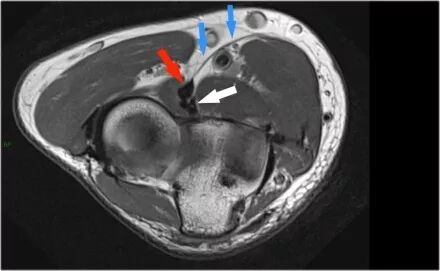

冠状图像上有一个美丽的UCL前束,但注意到关节内侧部分有骨赘形成(红色箭头)。当我们按照顺序向下看,可以看到存在一小部分低信号强度(黄色箭头),这是UCL的一部分撕裂。

这是在X线片可以更好地观察(黄箭头 )。

当我们看轴向扫描时,我们可以欣赏巨大的骨赘形成。请注意,尺骨神经(蓝色箭头)紧邻这些骨赘,这些可能指示尺神经出现病变。